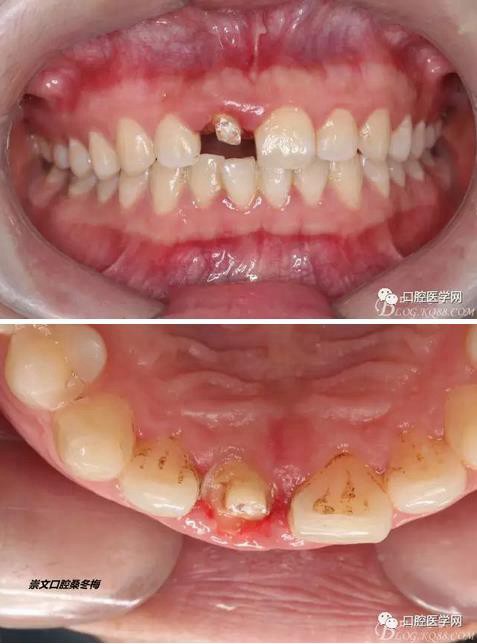

術(shù)前口內(nèi)照,11殘根,唇側(cè)牙齦紅腫,肩臺在齦下2毫米,舌側(cè)正常.21有被動萌出,長寬比例不協(xié)調(diào)。口腔衛(wèi)生一般,有菌斑。

術(shù)前原有牙冠復(fù)位,牙齦紅腫。